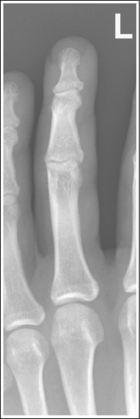

Finger: Posteroanterior Oblique Projection

See Figure 4-8 and Box 4-3.

The digit has been placed in a 45-degree PA oblique projection. Twice as much soft tissue width is demonstrated on one side of the digit as on the other side, and more concavity is demonstrated on one aspect of the phalangeal midshafts than on the other.

• A PA oblique finger is accomplished by rotating the affected finger 45 degrees from the PA projection (Figure 4-9). It is most common and comfortable for a patient to rotate the finger and hand externally to obtain a PA oblique finger projection, although internal rotation may be used when the second digit is imaged, to prevent a long object–image receptor distance (OID).

• Assessing accuracy of PA oblique projection. Study the amount of phalangeal midshaft concavity and soft tissue width demonstrated on PA oblique finger projections to verify the accuracy of rotation and to determine the proper repositioning movement needed when an oblique digit image shows too much or too little obliquity. A 45-degree oblique finger image demonstrates more phalangeal midshaft concavity and soft tissue width on the side positioned away from the IR. Use the soft tissue width to assess the degree of digital obliquity. If twice as much soft tissue width is present on one side of the digit as on the other, a 45-degree PA oblique projection has been obtained. If the phalangeal midshaft concavity and soft tissue width on both sides of the finger are more nearly equal, the finger was not rotated enough for the projection (see Image 3). If the soft tissue width on one side of the digit is more than twice as much as that on the other, and when one aspect of the phalangeal midshaft is concave but the other aspect is convex, the angle of obliquity was more than 45 degrees (see Image 4).

No soft tissue overlap from adjacent digits is present.

• Slightly spread the patient's fingers to prevent overlapping of the adjacent finger's soft tissue onto that of affected finger. Superimposition of these soft tissues makes it difficult to evaluate the soft tissue of the affected finger (see Image 5).

The IP and MP joints are visualized as open spaces, and the phalanges are not foreshortened.

• The IP and MP joint spaces are open and the phalanges are not foreshortened if the finger is fully extended and positioned parallel with the IR and perpendicular to the central ray. When the hand and fingers are positioned obliquely, some of the fingers are no longer placed against the IR but are positioned at varying OIDs. In this position the distal phalanges naturally tilt toward the IR. To keep the affected finger parallel with the IR and to maintain open joint spaces, it may be necessary to place an immobilization device beneath the distal phalanx. This is especially true when the second and third digits are imaged because they are at the greatest OID. It is also necessary to center a perpendicular central ray to the PIP joint to maintain open joint spaces. Failure to position the affected finger parallel with the IR and perpendicular to the central ray foreshortens the phalanges and closes the joint spaces (see Image 6).

The PIP joint is at the center of the exposure field. The distal, middle, and proximal phalanges and half of the metacarpal of the affected digit are included within the collimated field.

• Direct a perpendicular central ray to the PIP joint to place it in the center of the image. Open the longitudinal collimation to include the distal phalanx and the distal half of the metacarpal. Transversely collimate to within 0.5 inch (1.25 cm) of the finger skin line.

On both sides of the phalanx the soft tissue width and midshaft concavity are almost equal; the patient's finger was positioned at less than 45 degrees of obliquity for the image.

More than twice as much soft tissue width is present on one side of the phalanges as on the other. One aspect of the midshafts of the phalanges is concave, and the other aspect is slightly convex. Obliquity was more than 45 degrees for this image.

Soft tissue from an adjacent finger is superimposed over the affected finger's soft tissue; the fingers were not spread apart.

Spread the fingers until the adjacent fingers are positioned away from the affected finger.

The IP joint spaces are closed, and the distal and middle phalanges are foreshortened; the finger was not positioned parallel with the IR.

Position the finger parallel with the IR. It may be necessary to position an immobilization device beneath the distal phalanx to maintain accurate finger positioning. If the distal phalanx is of interest and the patient is unable to extend the finger, image it in an AP oblique projection, elevating the proximal metacarpals until the affected phalanx is aligned parallel with the IR and rotated 45 degrees.